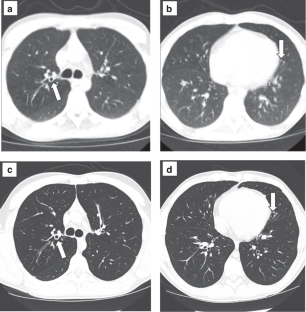

In all, 20 subjects (45% male, median age 18 years, median body mass index 22.7 kg/m2, and 45% F508del homozygous) completed baseline questionnaires and 17 completed ULDCT (median dose length product 6.6 milligray.cm) and post-ULDCT surveys. Findings revealed 13 subjects had bronchiectasis. Baseline surveys revealed 50% of participants reported not completing ACT the week prior to enrollment. Post-ULDCT, 82% reported completing ACT in the prior week. Reported unintentional and purposeful nonadherence to ACT decreased post-ULDCT.

ULDCT identified a high rate of bronchiectasis among PwCF taking ETI in this study.